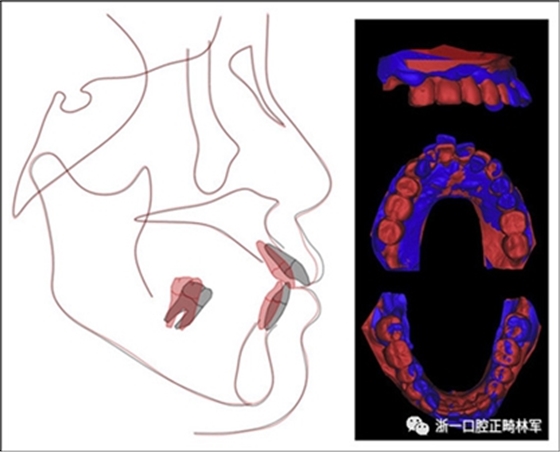

治療后頭影測量分析顯示上頜切牙的傾斜和唇部相對于E線的位置都得到改善(表II)。治療前后頭影測量圖的疊加顯示上頜和下頜切牙的向后移動伴隨著上頜切牙的推入。垂直維度在跨學(xué)科正畸綜合治療后被保持。三維模型的疊加顯示了上頜牙列的遠(yuǎn)中移動,下頜前牙的回縮和上頜右側(cè)尖牙的推入(圖14)。

圖14.頭影測量和3維模型的疊加